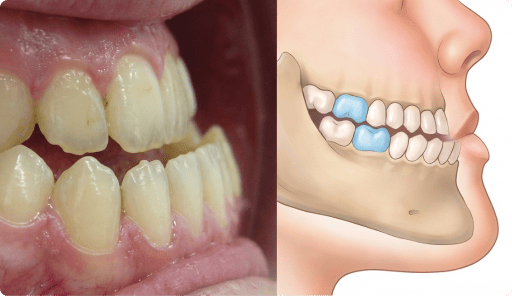

Posterior cross-bite

Upper jaw growth → Corrected reverse bite

“Her lower jaw covering upper jaw, how can Dr help with this?”

Clinical observation

Upper jaw is under-developed.